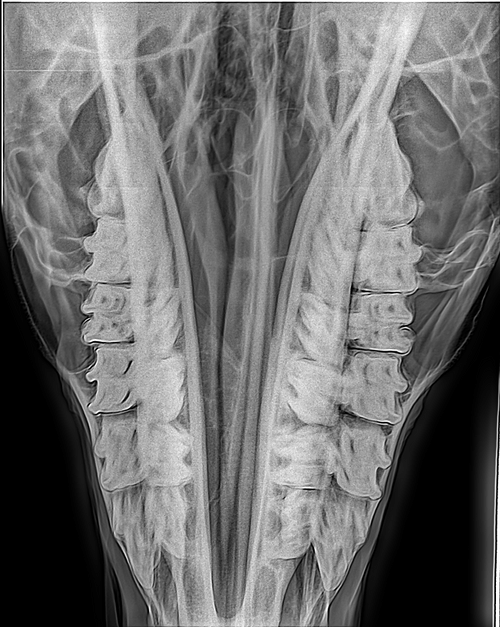

Aus der modernen Pferdemedizin nicht mehr weg zu denken, dient das digitale Röntgen auch in der Zahnheilkunde als wichtiges diagnostisches Mittel. In verschiedenen Ebenen geröngt, können Befunde im Bereich der Zähne, der Nebenhöhlen und des Schädels erhoben werden.